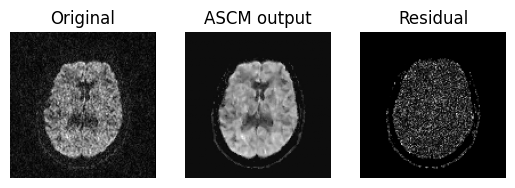

To access the quality of this denoising procedure, we plot an axial slice of the original data, it’s denoised output and residuals.

Showing the axial slice without (left) and with (middle) ASCM denoising.

From the above figure we can see that the residual is really uniform in

nature which dictates that ASCM denoises the data while preserving the

sharpness of the features. Now, we are Saving the entire denoised output in

denoised_ascm.nii.gz file.